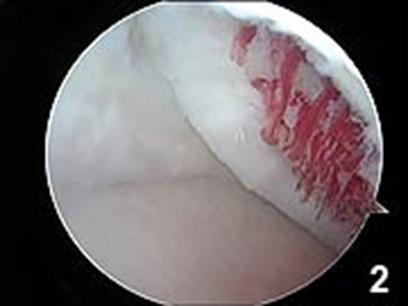

Dupa indepartarea cu succes a stratului de cartilaj calcifiat, o andrea este folosita pentru a face mai multe gauri mici (mirofracturi) in osul expus al defectului condral aflate la distanta de 1-2 mm. Trebuie lasata o punte de oase potrivita intre gauri. Tehnica de microfracturi are numeroase avantaje fata de foraj. Mai intai de toate, creaza o leziune termala mai mica. Mai mult, cu microfracturi chirurgul este capabil sa intre in zonele dificile ale suprafetei articulare cu un control mai bun asupra adancimii de patrundere. La finalizarea microfracturii, o suprafata aspra este generata pentru aderenta cheagului de sange care contine celule mezenchimale nediferentiate de la osul subcondral. Trebuie avut grija ca cele mai marginase parti ale leziuni sa fie patrunse de andrea pentru a ajuta la vindecarea tesutului reparator la imprejmuirea suprafetei articulare. Odata ce microfractura este finalizata, pompa artroscopica este oprita pentru a se asigura ca sangerarea maduvei curge din gaurile mici umpland defectul.[54]

Operatia a fost executata doar de catre chirurgii care au fost pregatiti si au avut experienta cu tehnica de microfracturare. A fost facuta in fiecare caz o artroscopie minutioasa cu scopul de a identifica eventualele anormalitati aditionale intra articulare. Singura leziune gasita la 21% din pacienti a fost ruptura partiala de menisc. Sase leziuni de menisc au fost localizate in acelasi compartiment cu leziunea cartilajului. Toate leziunile de menisc au fost tratate cu meniscectomie partiala. Microfracturile cartilajului lezat au fost executate dupa o metoda descrisa de Steadman. Asta include debridarea cartilajului lezionat, o indepartare atenta a invelisului calcifiat al cartilajului si micropenetrarea osului subcondral folosind instrumente specifice (Linvatec, Largo, Florida). Se mentine o distanta de 4mm intre micropenetrari pentru a asigura integritatea si functia osului subcondral. Eliberarea sangelui si a maduvei prin gaurile microfracturilor este confirmata prin eliminarea presiunii pompei artroscopului. La pacientii cu leziuni ale condilului femural, miscarea pasiva continua incepe din camera de recuperare de la 0º la 60º si este crescuta gradual pana se obtine miscarea pasiva completa. Se executa timp de 6 ore pe zi vreme de 6 saptamani. Evitarea incarcarii este mentinuta timp de 6 saptamani. Pacientii cu leziuni trohleare au fost lasati sa incarce greutatea suportabila si miscarea a fost evitata pentru 48 de ore. Apoi a fost permisa incarcarea cu intreaga greutate, cu toate ca flexia activa a fost limitata la 0º la 20º; totusi, miscarea pasiva activa de la 0º la 80º a fost utilizata timp de 6 saptamani. Bicicleta ergonomica a fost utilizata imediat ce posibilitatea de miscare o permite. Intreaga greutate a corpului pe genunchiul operat a fost permisa dupa 7-8 saptamani de la operatie, iar intoarcerea la activitatile regulate dupa 6-8 luni postoperator.